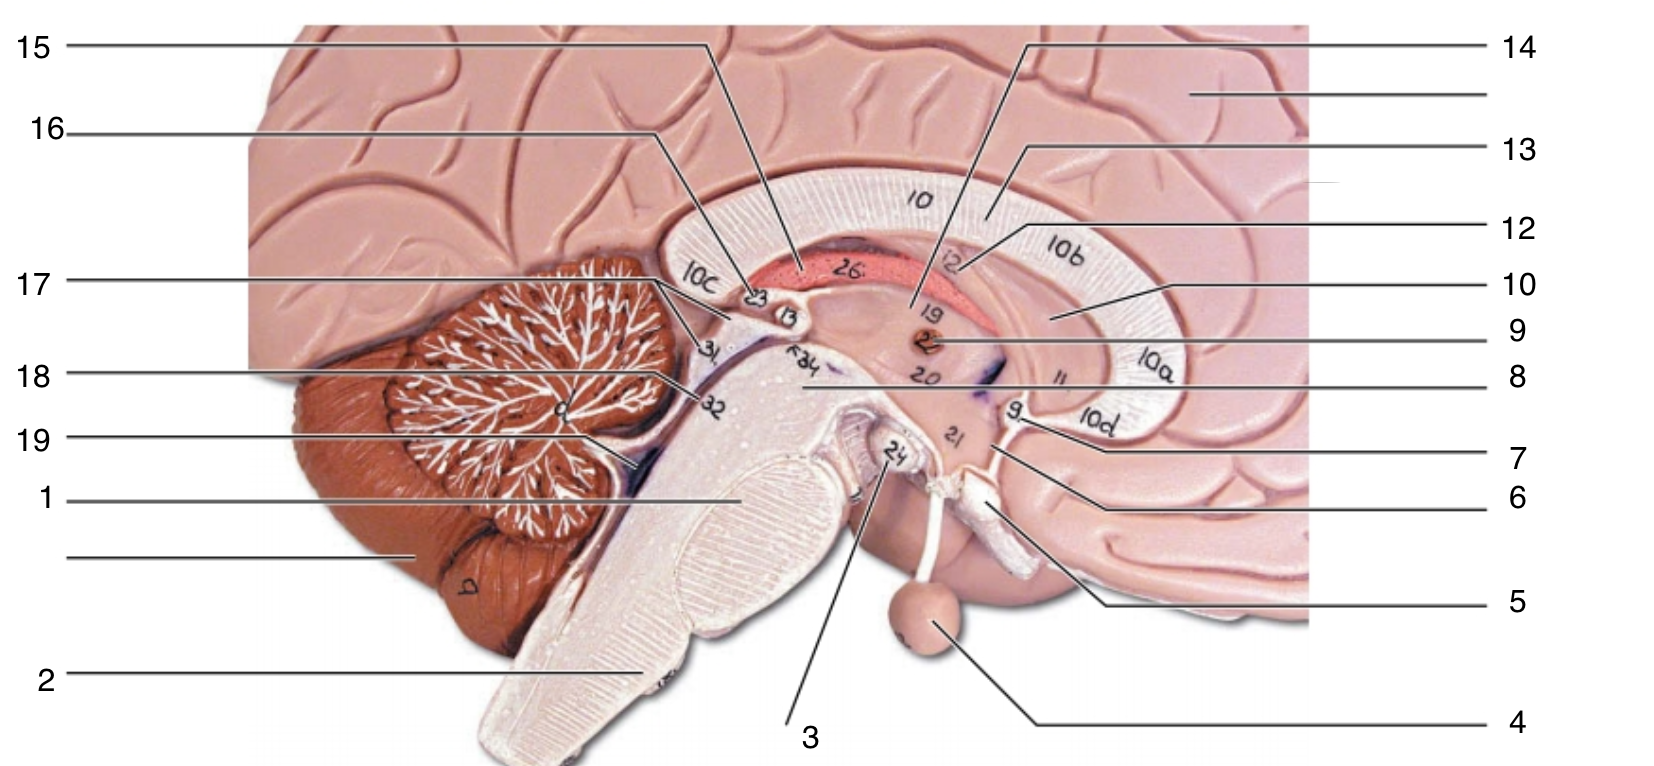

Brain Stem

1

pons

1

2

medulla oblongata

2

3

mammillary body

3

4

pituitary gland

4

5

optic chiasma

5

6

hypothalamus

6

7

anterior commissure

7

8

midbrain

8

9

interthalamic adhesion

9

10

septum pellucidum

10